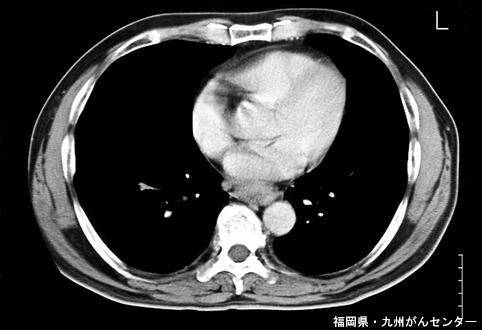

질환(병리주체)의 분류 악성 상피성종양/편평상피암

부위(장기별) 식도/하

검사방법 CT

종양의 육안분류 2형(궤양국한형)/

종양의 최대경(밀리미터) 40이상

종양의 심달도 s(a)